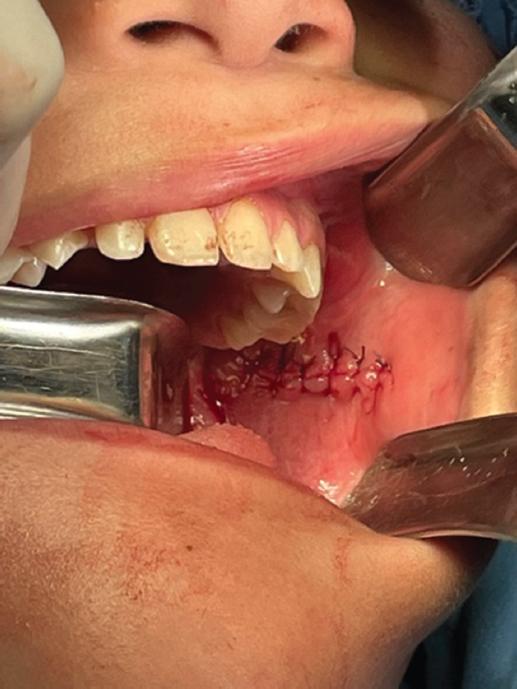

A continuación se identificaron los límites anatómicos: papila del conducto de Stenon y línea alba de la mordida en el carrillo. Se realizó una incisión de 1 cm en el punto intermedio de estas dos estructuras utilizando una hoja de bisturí del n.º 15 (Fig. 3); para lograr una mejor visualización se amplió la incisión anteriormente hasta alcanzar los 4 cm de longitud, lo que permitió la visualización del espacio bucal y masticatorio. A continuación, se realizó disección roma hasta visualizar el músculo buccinador, para continuar con la disección a través de este, separando el tumor del espacio bucal, pterigoideo e infratemporal izquierdo (Fig. 4).

Figura 3 Disección roma hasta llegar a visualizar el musculo buccinador para continuar la disección a través de él.